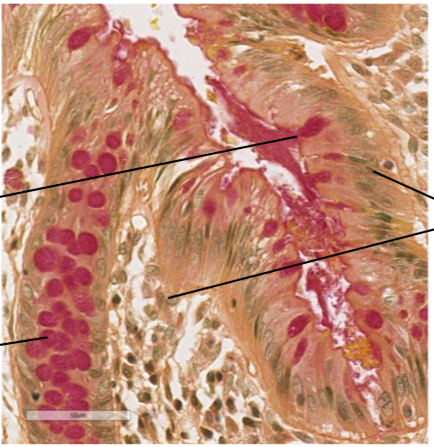

dans quelle structure plus importante du poumon on retrouve ce qui est sur cette lame et donne également les parties en noir

on retrouve les alvéoles et les sac alvéolaires au niveau du parenchyme pulmonaire

En noir du plus haut au plus bas :

capillaire (on y percoit les globules rouges)

paroi alvéolaire (faite de fibre élastique)

Pneumocyte de type 2 (les cellules un peu plus grosses)

cellules endothéliales ou pneumocytes de type 1 (plus petites)